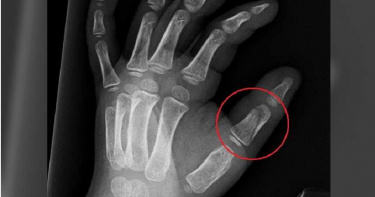

臺北市私立長欣文理技藝短期補習班(簽約加盟快樂瑪麗安美語教學體系,而使用「快樂瑪麗安南海分校」之名義招生,已結束經營)負責人林漢凌及2名女老師劉蕓德、金智儀,從民國95年底起對校內1名2歲男童施暴,直到該男童上小學三年級為止,時間長達7年。3人除體罰、帶頭霸凌外,更以壓頭嗆水、空拋、提供腐敗食物、禁止上廁所等方式凌虐男童。最高法院依妨害幼童發展罪判負責人2年4個月徒刑。2女老師一審獲判6個月,得易科罰金後未上訴。全案定讞。判決書指出,林漢凌身為安親班與幼稚園的負責人,卻與2名老師對男童施暴,造成男童就讀該校6年期間遭遇地獄般生活。3人除常用「愛的小手」敲打男童頭部及身體,還常故意把男童頭部壓進水桶或水池,使其嗆水,或命令半蹲、交互蹲跳、四肢撐椅做「桂河大橋」,與曾在冬天命令男童脫光再用冷水沖,甚至抓住腳踝旋轉甩出,先撞到牆,後來摔到地板上,造成男童左拇指骨折。3人還會命令男童洗廁所,以及稱男童母親在醫院工作,所以男童身上有病毒、尿有細菌,命令男童上課戴口罩,其他學童不用,造成男童遭同學排斥,甚至無故禁止男童吃午餐、點心,或提供發霉、腐敗酸辣湯,以及禁止喝水、小便。男童母親多次詢問負責人孩子經常受傷原因,但都遭負責人搪塞,且負責人事後還變本加厲虐待,導致男童回家不敢告訴家人,直到小學3年級才拜託父母轉至其他分校。男童之後透過報導得知「南海分校」有其他幼童受虐,並因回憶過去產生身心異狀,就醫後被診斷出PTSD,隨後說出自身遭遇。男童出庭時指證負責人及2名女老師施虐,其中劉蕓德、金智儀坦承虐待男童,但負責人林漢凌辯稱「沒必要對花錢來就讀的男童做這些事,也沒要求老師虐待他」,聲稱是男童及挾怨報復的離職老師編造不實指控。2020年一審法官判負責人3年10個月;2女師各6個月,得易科罰金18萬。負責人單獨上訴後,雖表示願意賠償20萬,但無法與家屬達成共識,二審高院改判2年4個月。負責人再度上訴後,遭最高法院駁回,全案定讞。◎《CTWANT》關心您,若懷疑孩童遭受身體虐待、精神虐待或是性侵害、性騷擾,請撥打113專線

連鎖安親班女老闆林漢凌和2名女老師劉蕓德、金智儀聯手,凌虐一名男童長達7年。林漢凌手法殘忍,多次以學童不聽話、尿褲子為由虐待學童,並指使劉、金姓老師對學童施暴,對學童浸水桶、餵食發霉的點心以及辣椒等,而她矢口不認罪,甚至還向其他人稱自己最愛該名學童。法院2024年2月依妨害幼童發育罪判林女2年4月徒刑定讞,林女今早向台北地檢署報到,發監執行。2名女老師先前均已判刑6月、得易科罰金18萬元定讞。這起虐童案爆發於2014年年底,多名家長聯合控訴林漢凌所開設的安親班虐待學童。遭虐的男童家長表示,男童曾多次表明要換安親班,直到看到新聞畫面以及其他家長告知,才得知男童長年遭到老師虐待。判決書指出,該名男童遭受老師多種施虐,她們故意會將男童頭部強壓進裝水的水桶他嗆水,還逼男童吃發霉點心、喝腐壞結塊牛奶,哄騙切碎的辣椒是番茄誘導男童吃下,甚至在冬天逼男童脫光,用冷水沖灑他身體,還常要求男童去做搬書、刷廁所、刷課椅等粗重工作,限制他不准尿尿、喝水等,倘若男童犯錯,便會用「愛的小手」將他打至遍體鱗傷。男童母親雖發現兒子經常受傷,多次詢問負責人林女,但林女都會編理由搪塞過去,事後再變本加厲傷害男童,導致男童後來即使遭受虐待,也不敢告訴母親,直到男童9歲時拜託媽媽把他轉到其他安親班,虐待才告一段落。後來,男童看到媒體報導林女的補習班有其他幼童遭虐待,想到自己先前7年的遭遇,身心爆發異狀,父母帶男童就醫,被診斷出罹患創傷後壓力症候群,男童才說出自己的悲慘遭遇。法院審理時,男童證稱林女跟2名女老師都曾抓住他的腳踝一直旋轉,甩到男童跟地面平行時,再突然放手把他扔出去,還因此摔斷男童左手大拇指。至於其他恐怖的凌虐方式,男童也都一一告訴法官。法庭上,2名女老師承認曾傷害男童,但林漢凌始終堅稱自己沒有必要對花錢來就讀的男童做這些事,也沒要求老師虐待他,是男童及離職後挾怨報復的其他老師編造不實指控。法院一審依妨害幼童發育罪判林女3年10月徒刑,劉姓、金姓女老師各判刑6月,得易科罰金18萬元,僅林女上訴。高院審理時,林女表示願意賠償男童及父母20萬元,但因賠償金額無法達成共識,和解破局,二審改判林女2年4月徒刑,林女不滿再提上訴,2024年2月遭最高法院駁回定讞,台北地檢署日前發出執行通知書,17日上午林女到北檢執行科報到,發監執行。